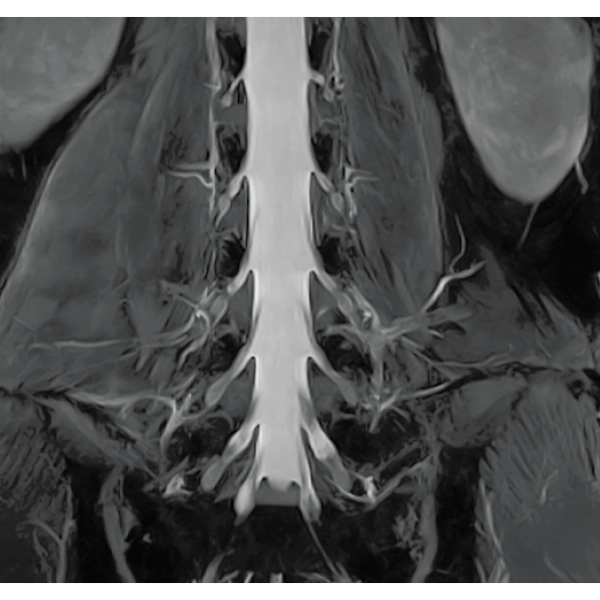

Imperfect imaging data to be better image quality through post-processing

By providing functions to remove and suppress artifacts in the imaging data and to generate reconstructed images from limited imaging data, it reduces the re-imaging rate and supports the realization of smooth MRI examinations.

Reduce artifacts caused by patient movement, such as coughing or sneezing, by post reconstruction.

Improving SNR and reducing wrap-around artifact through post reconstruction.

Even if the examination is interrupted, the minimum necessary data can be reconstructed later.

When motion artifacts occurs in the image due to coughing, sneezing, or involuntary movements, either or both the visual information acquired by monitoring cameras, Synergy Vision, and the intrabody information acquired by the navigator pulse can be used to provide an image with reduced artifacts. This reduces the re-imaging rate.

Body movements that affect image quality are detected from monitoring cameras based on thresholds derived for each body part.

Movements within the body are detected by navigator pulses. Body movements that significantly affect image quality are detected based on the error between pulses.

Deep Learning technology*8 enables image quality adjustment after imaging is complete. It optimize SNR and improve image sharpness by processing MRI signals in stages (k-space signal processing). This brings super-resolution and reduces truncation artifacts.

When the size in the phase encoding direction is incorrectly set , the signal outside the FOV will fold back and appear as artifacts in the image. Exp. RAPID reconstructs the image according to the specified FOV magnification ratio. Artifacts can be removed in post-processing.